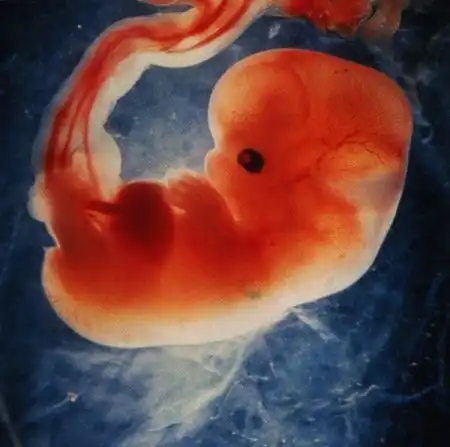

У мамы в животике)